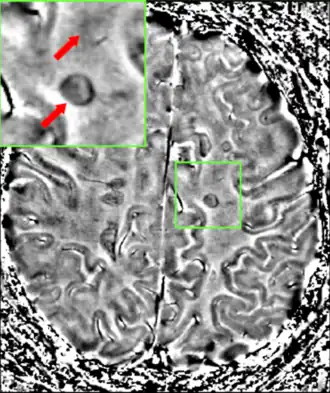

MRI brain scan produced using a Gradient-echo phase sequence showing an iron deposit in a white matter lesion (inside green box in the middle of the image; enhanced and marked by red arrow top-left corner)[232]

Improvement in neuroimaging techniques such as positron emission tomography (PET) or MRI carry a promise for better diagnosis and prognosis predictions. Regarding MRI, there are several techniques that have already shown some usefulness in research settings and could be introduced into clinical practice, such as double-inversion recovery sequences, magnetization transfer, diffusion tensor, and functional magnetic resonance imaging.[235] These techniques are more specific for the disease than existing ones, but still lack some standardization of acquisition protocols and the creation of normative values.[235] This is particularly the case for proton magnetic resonance spectroscopy, for which a number of methodological variations observed in the literature may underlie continued inconsistencies in central nervous system metabolic abnormalities, particularly in N-acetyl aspartate, myoinositol, choline, glutamate, GABA, and GSH, observed for multiple sclerosis and its subtypes.[236] There are other techniques under development that include contrast agents capable of measuring levels of peripheral macrophages, inflammation, or neuronal dysfunction,[235] and techniques that measure iron deposition that could serve to determine the role of this feature in MS, or that of cerebral perfusion.[235]